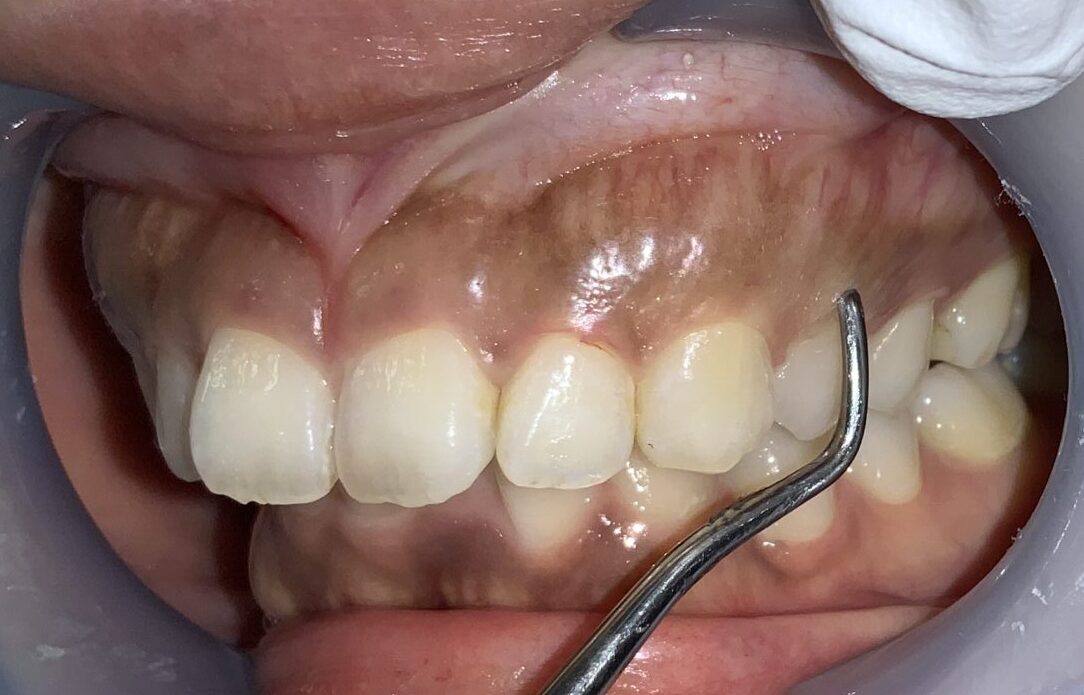

今度は犬歯です。この歯は大きく切り取ってしまうと「八重歯」みたいになってしまうので、歯ぐきを整形するときに注意が必要な歯です。

歯ぐきが被っている量や厚みはたくさんあります。

前歯に戻って反対側です。

こちらも歯槽骨のざらざら感や、とがった部分がありそうです。

犬歯です。通常は大きく見えるはずなのに、たくさんの歯ぐきが被ってしまっていて、とても小さくなっている犬歯です。